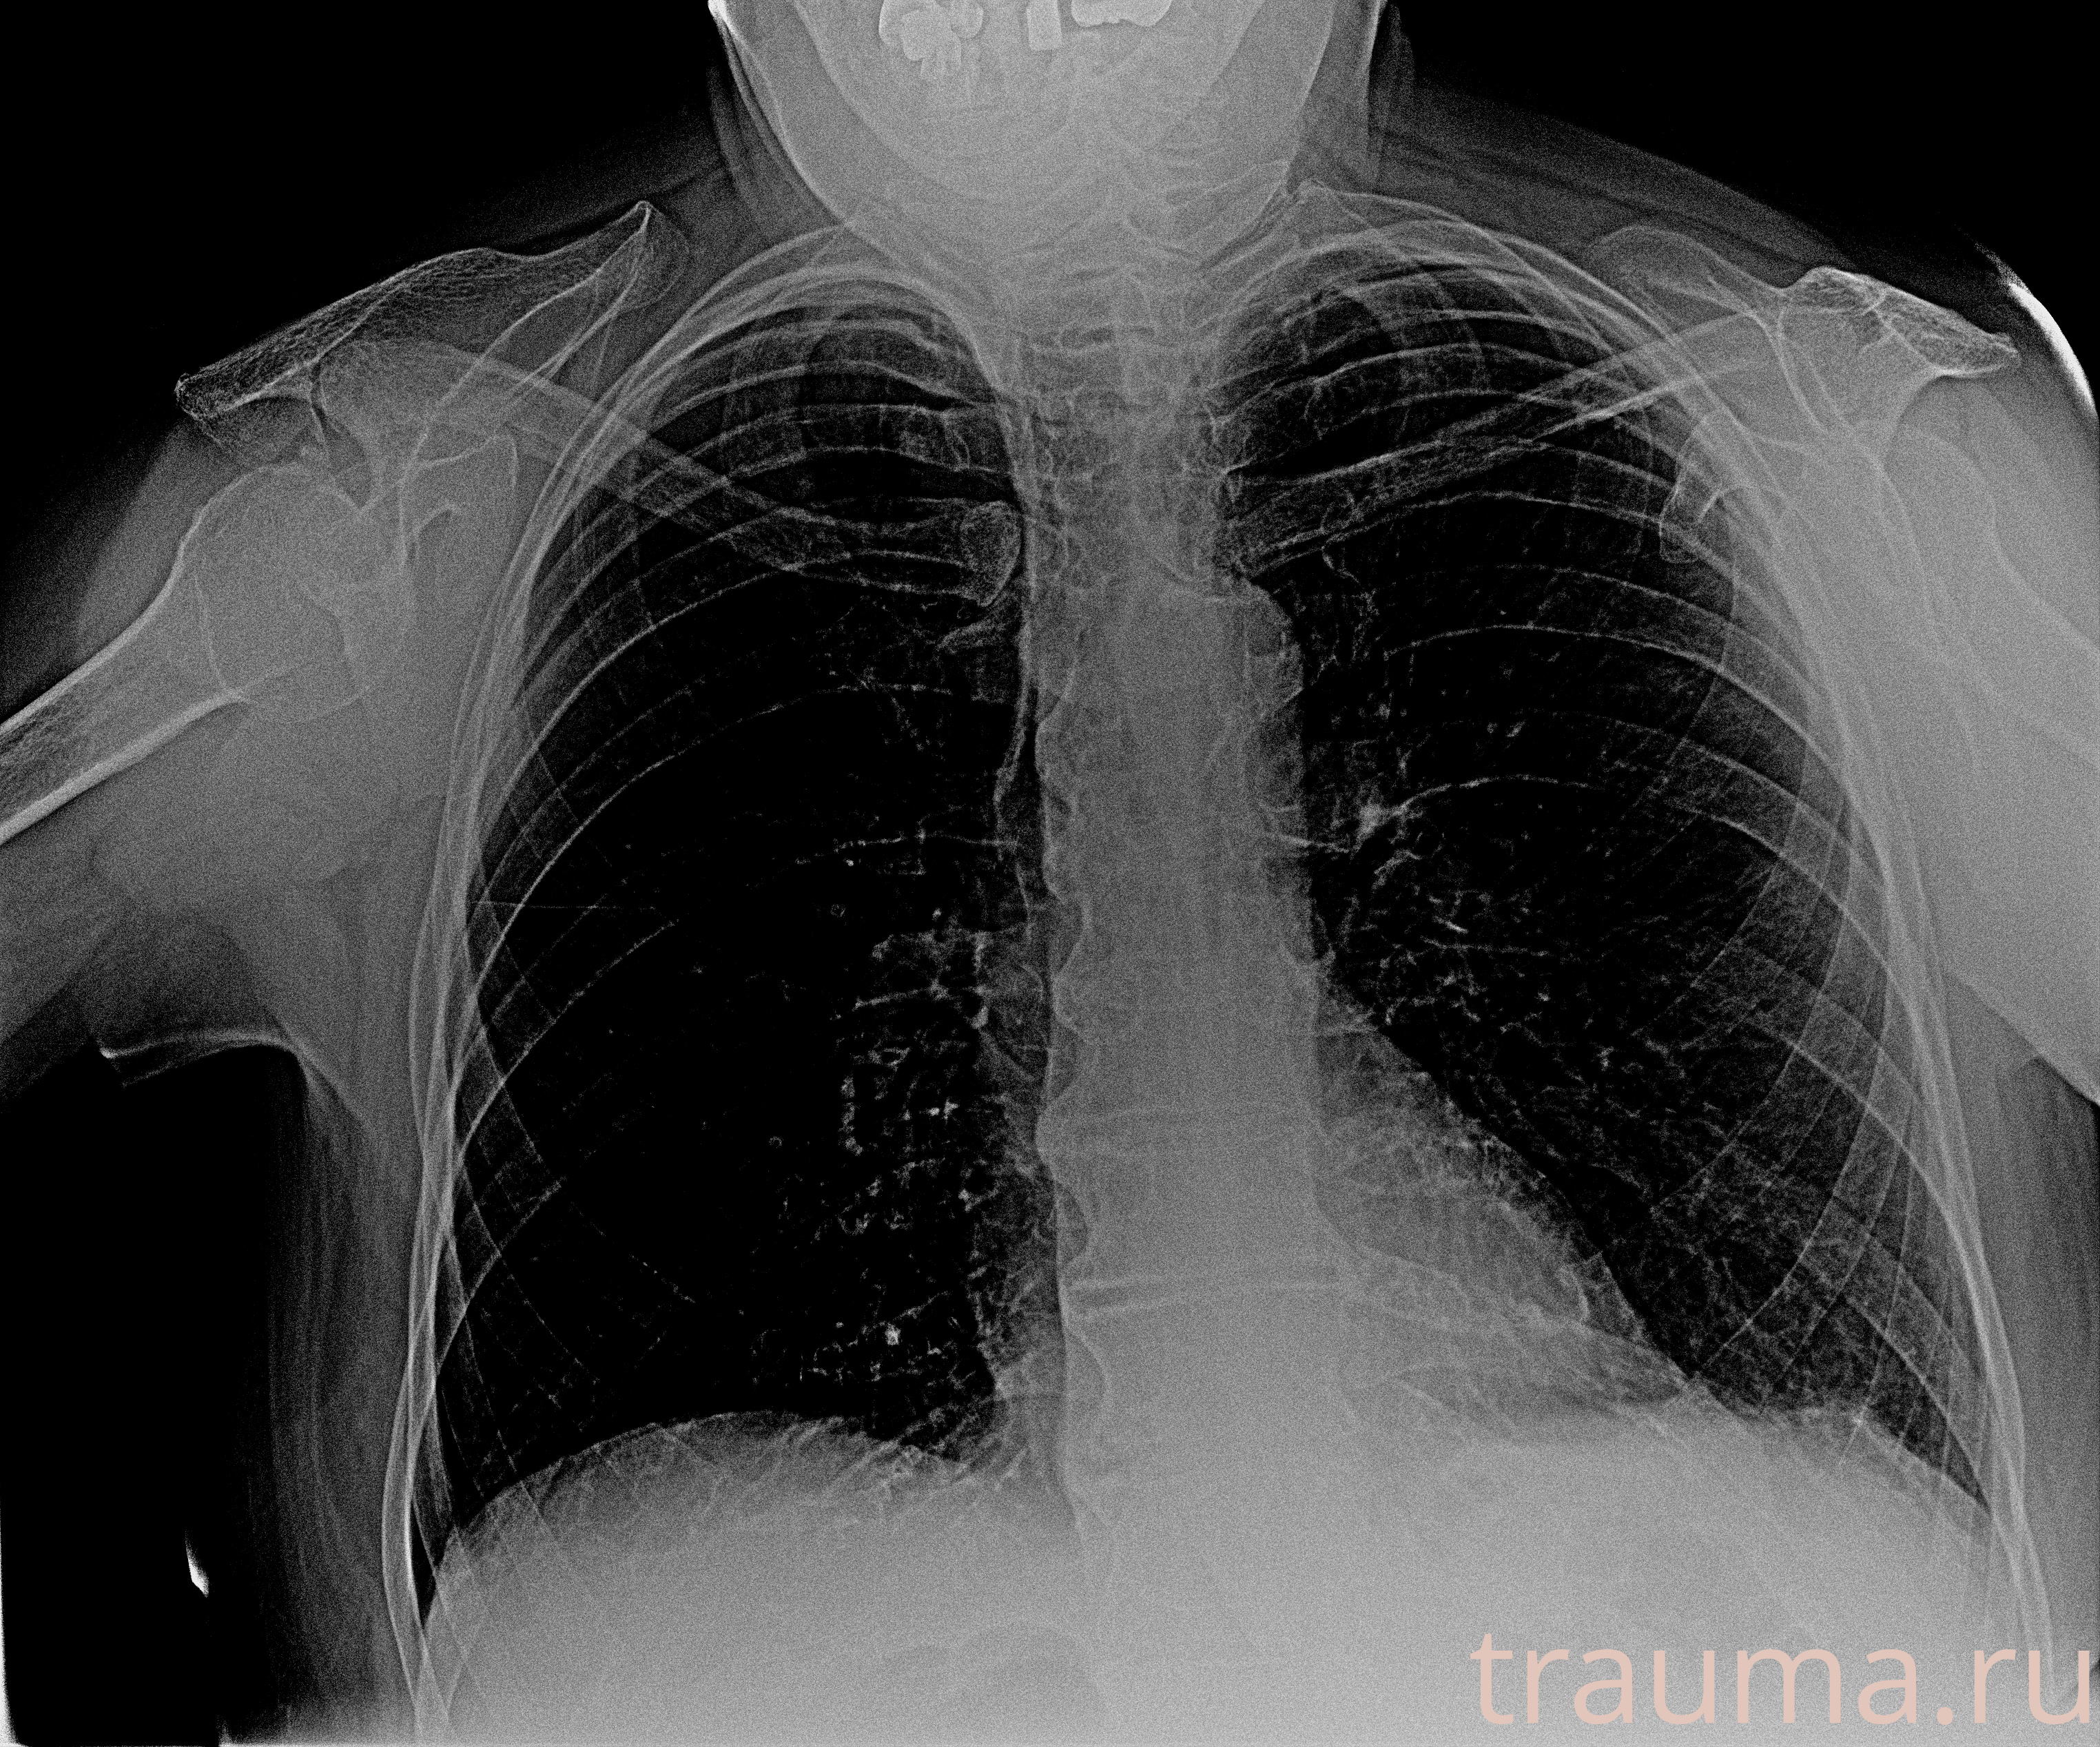

Рентген на дому: по вашему адресу приезжает врач-рентгенолог, травматолог-ортопед с мобильным рентгеновским аппаратом, проводит диагностику травмы или заболевания, делает необходимые рентгенограммы, дает рекомендации по дальнейшему лечению. Получить качественные снимки в домашних условиях возможно благодаря уникальной методике, разработанной МосРентген Центром для института  Склифосовского

при переломе шейки бедра и пневмонии от компании МосРентген Центр - партнера Института имени Склифосовского